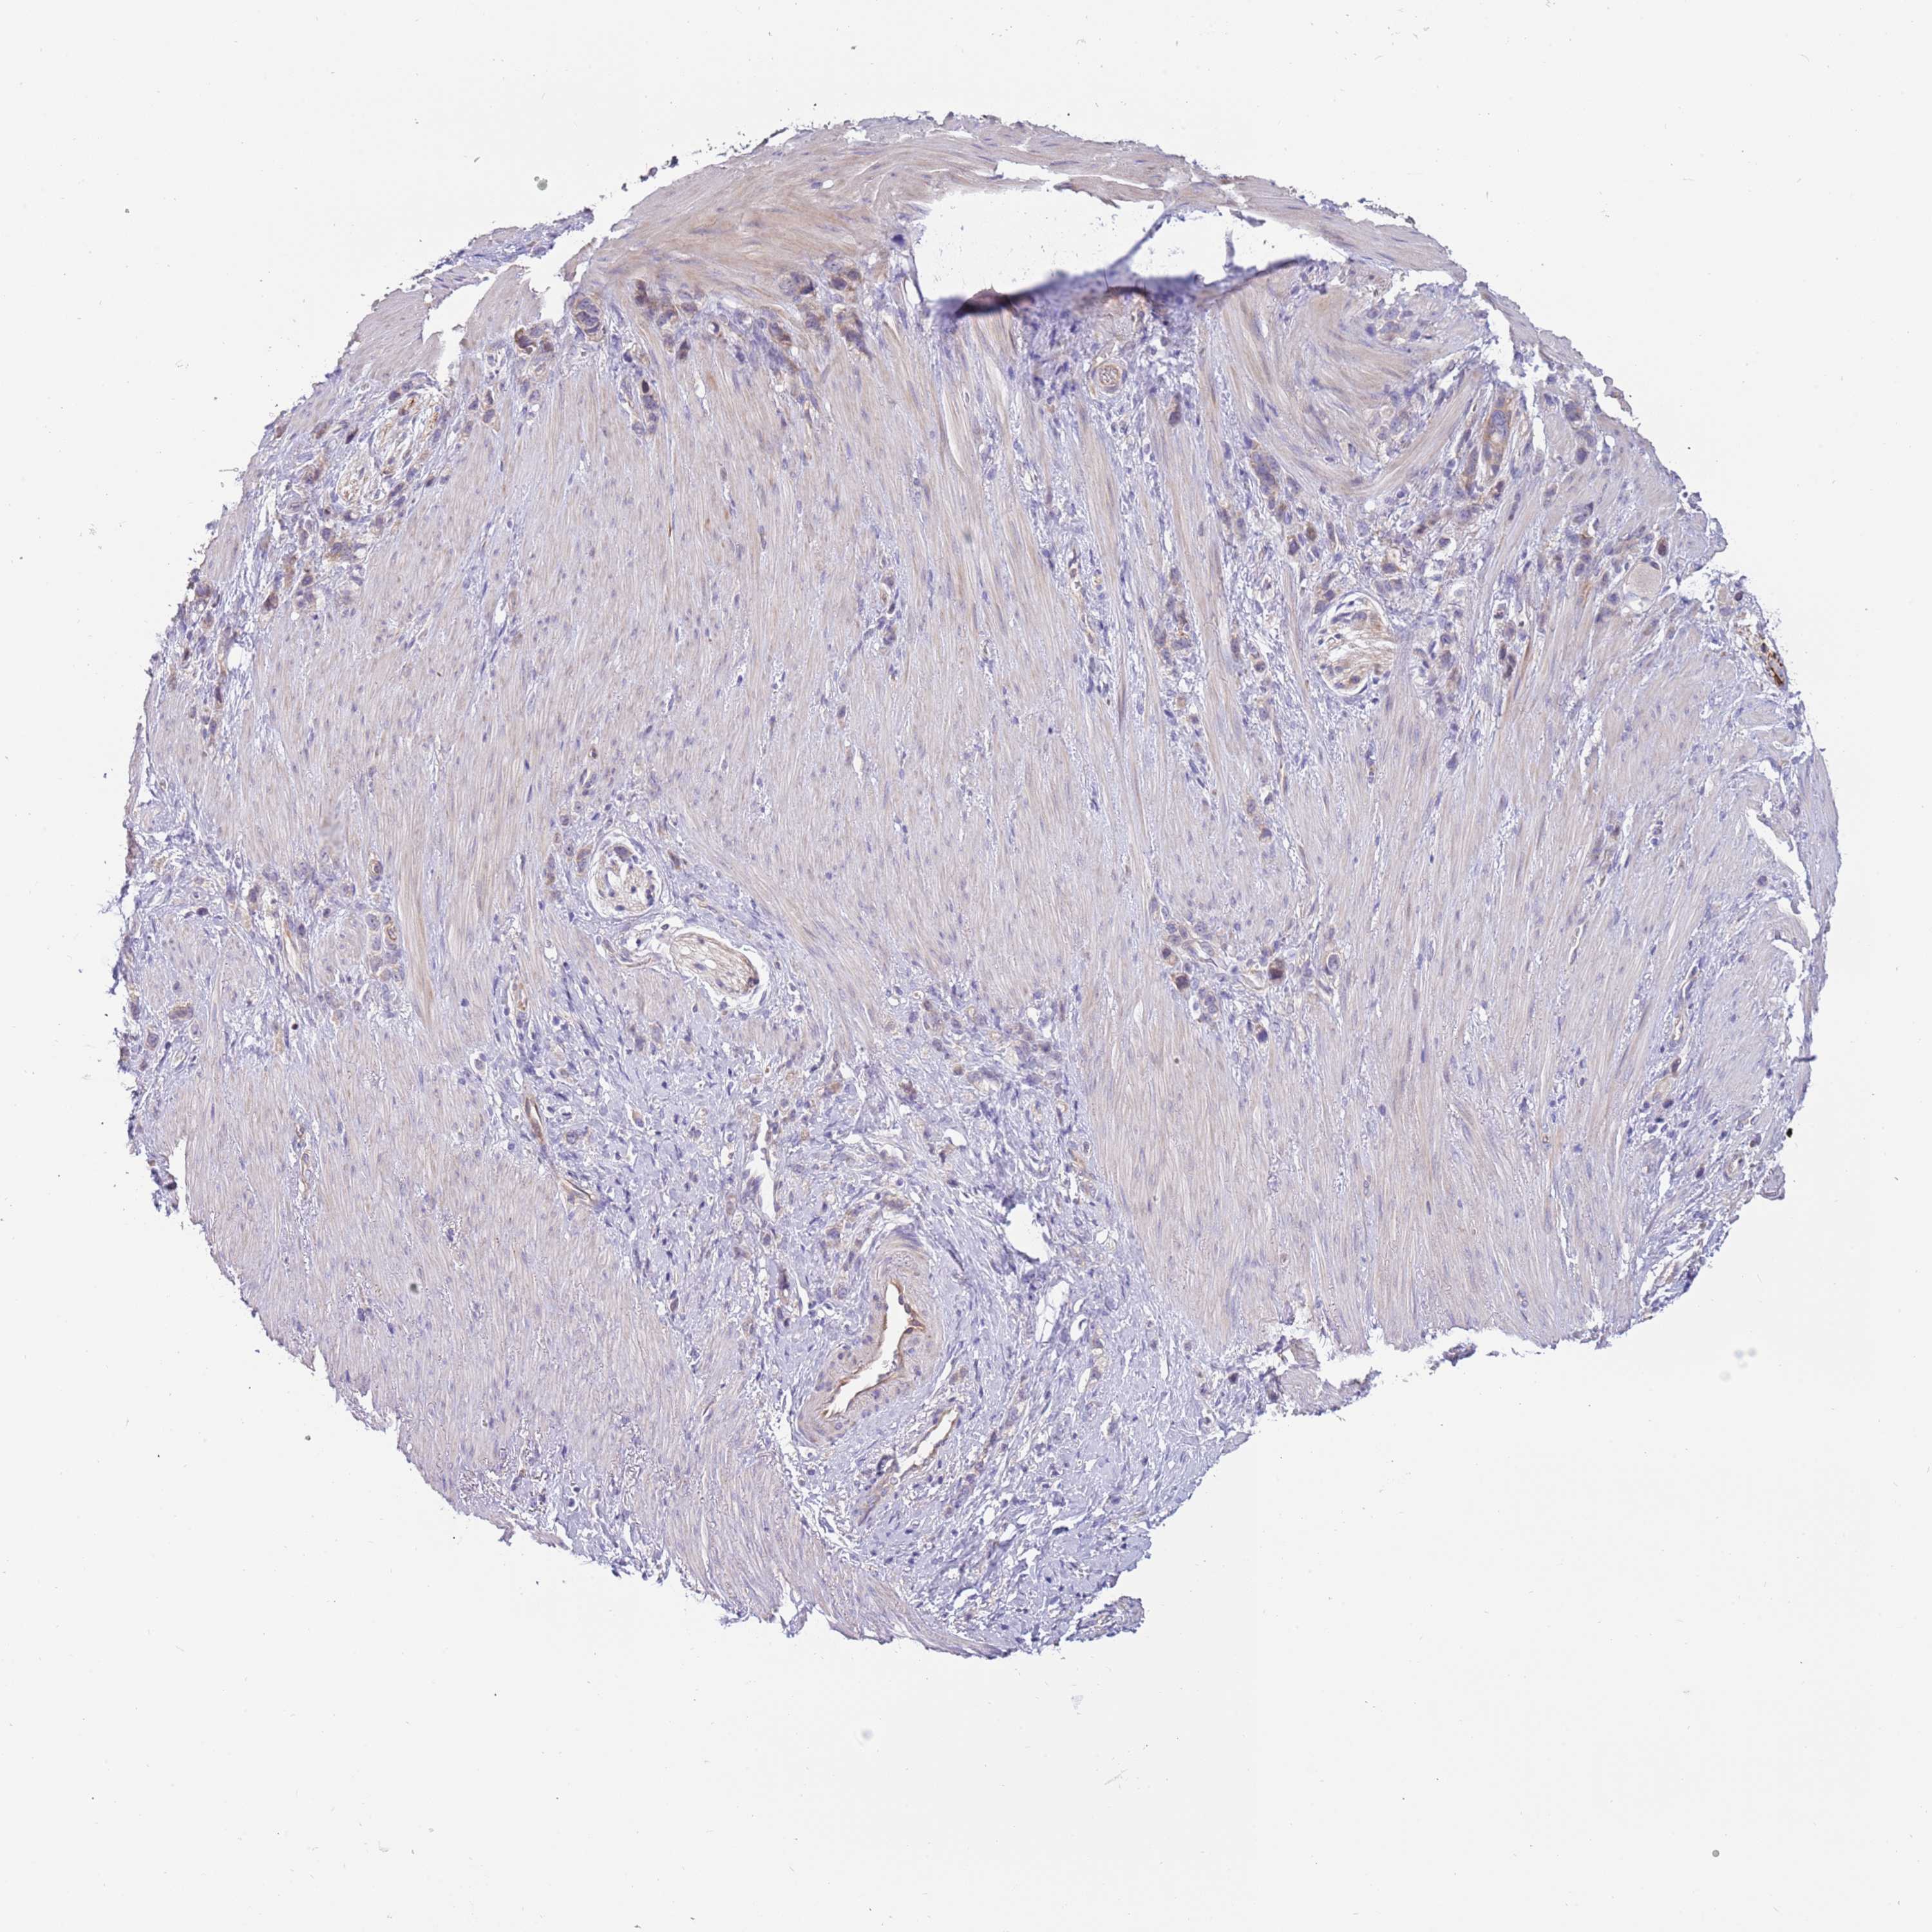

STOMACH CANCER - Protein expressioni

A mouse-over function shows sample information and annotation data. Click on an image to view it in a full screen mode. Samples can be filtered based on level of antibody staining by selecting one or several of the following categories: high, medium, low and not detected. The assay and annotation is described here.

Antibody stainingi

Antibody staining in the annotated cell types in the current human tissue is reported as not detected, low, medium, or high, based on conventional immunohistochemistry profiling in selected tissues. This score is based on the combination of the staining intensity and fraction of stained cells.

Each image is clickable and will lead to virtual microscopy that enables deeper exploration of all samples and also displays staining intensity scores, fraction scores and subcellular localization as well as patient and tissue information for each sample.

Antibody HPA040703

Antibody HPA047801

Staining

High

Medium

Low

Not detected

Intensity

Strong

Moderate

Weak

Negative

Quantity

>75%

75%-25%

<25%

None

Location

Nuclear

Cytoplasmic/membranous

Cytoplasmic/membranous,nuclear

Adenocarcinoma, NOS

Adenocarcinoma, High grade